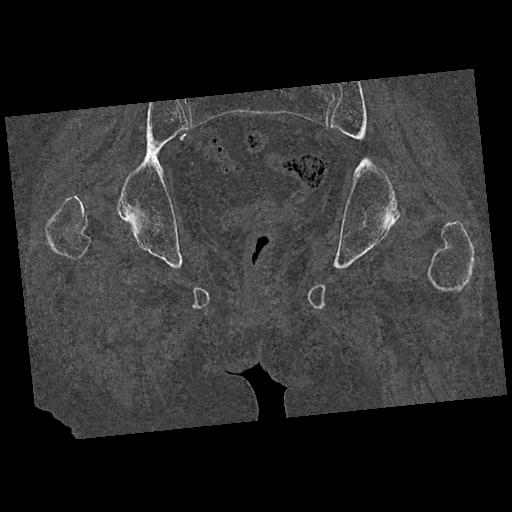

100703 1/27 両股正面+軸 1/29 両股正面+軸 94歳女性 パンソンロン